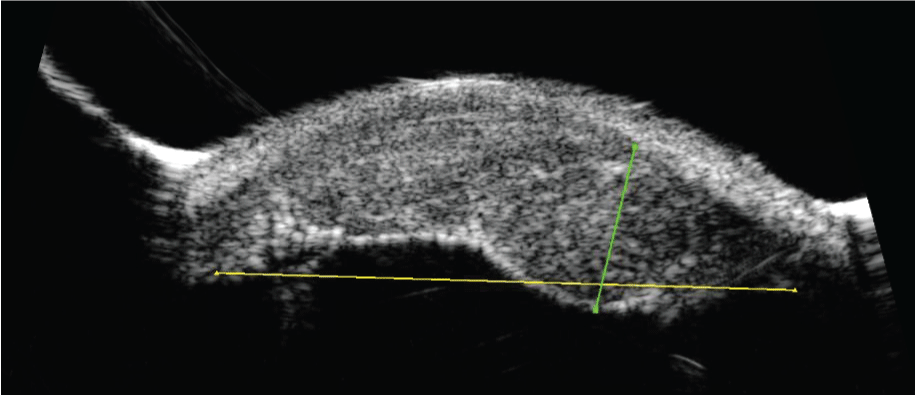

A 56-year-old man presented for evaluation of an iris nevus (Figure 1A). Unilateral ocular hypertension was found on outside exam requiring timolol to maintain the intraocular pressure at 19. Ultrasound biomicroscopy of the nevus demonstrated a 4 × 1 mm lesion without angle or ciliary body involvement (Figure 1B). The patient did not return for follow up and was treated for recalcitrant unilateral glaucoma during this time with a trabeculectomy and implantation of two glaucoma drainage devices.

Figure 1b: Ultrasound biomicroscopy across width of initial lesion depicting flat lesion above iris not involving the ciliary body or angle.